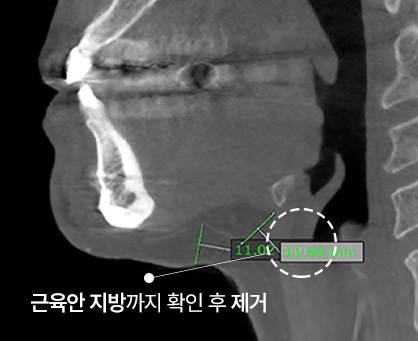

3D-CT를 통한 지방량 측정 후

턱 밑 최소 절개

근육과 근막 사이에 쌓인

근육 안쪽 지방 제거 및

느슨해져 있는 깊은 목 근막 타이트닝

근육 안쪽 지방까지 제거하여

더욱 확실한 V라인!

손으로 만지고 눈으로 보는 진료가 아닌 3D-CT로 피부 속, 근육 밑 상태까지

면밀하게 파악하며 개인별 피부 조직의 두께, 주름의 방향, 피부 처짐의 정도까지

세밀한 진단을 통하여 목주름의 형태별로 맞춤 솔루션을 제안합니다.

얼굴 속 숨은 지방층까지 3D-CT로 정확하게 체크

이중턱착붙리프팅은 두툼한 턱살, 가로목주름, 세로목주름을 모두 개선할 수 있는 방법으로 턱 라인을 밋밋하게 만드는 피하지방 제거와 리프팅을 동시에 진행하여 목선과 턱 라인을 이상적으로 만들어냅니다. 턱 밑 최소 절개 후 피하지방 뿐만 아니라 근육 안쪽 지방까지 흡입하여 목 라인을 더욱 길게, 주름 개선 및 V라인에 도움을 줍니다.